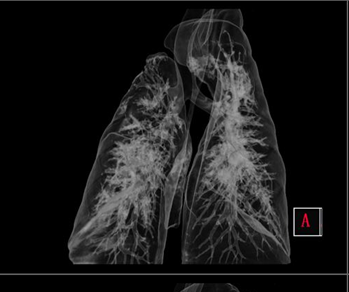

• Poumon